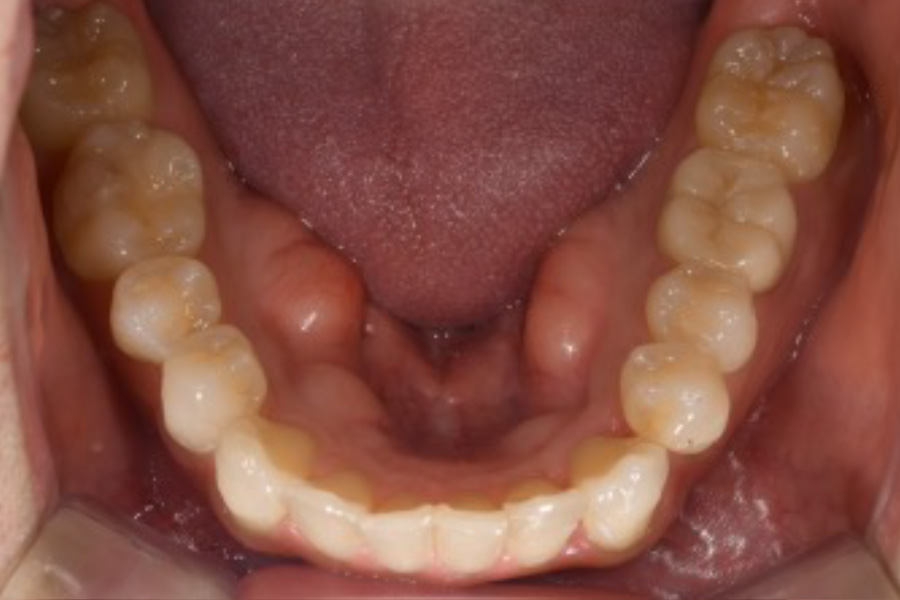

治療前

治療後

主訴 八重歯を含めた全体的なガタつき

治療内容 目立ちにくいマウスピース矯正(非抜歯矯正)

歯と歯の間に隙間をつくることにより、歯列弓を広げながら治療を行いました。